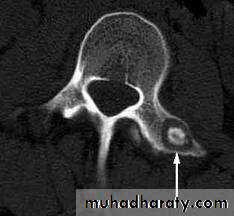

Plain x-ray

Show local sclerotic thickening of the shaft that may obscure the small central nidus within the area of rarefaction.The nidus is best seen on a fine cut CT scan

Intense uptake on an isotope bone scan.

Imaging13

C T scan